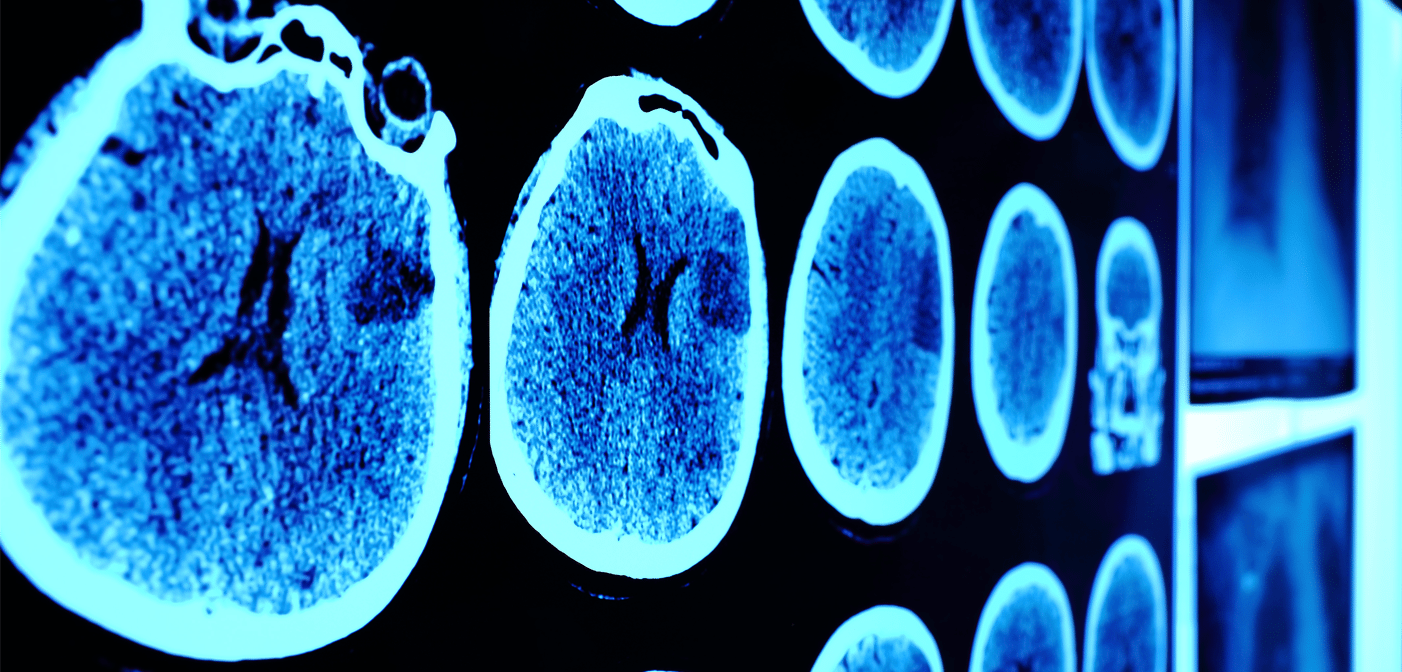

That’s right: Stress is a potent cause of neurodegeneration. The brains of people who are chronically fatigued show signs of shrinking, which means stressed executives have about the same brain capacity as people decades older.

This deterioration of critical brain regions hinders memory processing, strategic planning, and the ability to manage anxiety, which are all crucial skills for the executive. The deficiencies can knock you out of the game. Mental sharpness and the ability to innovate, collaborate, and connect are the price of admission in today’s world.